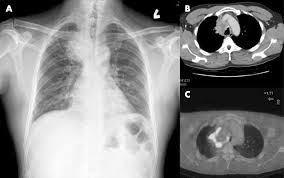

Teknik pemeriksaan radiology CT SCAN Abdomen dan CT Scan Thorax

BERIKUT teknik pemeriksaan ct scan thorax dan abdomen bisa anda simak di presentasi dibawah ini: